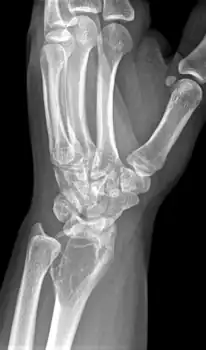

On X-ray, giant-cell tumors (GCTs) are lytic/lucent lesions that have an epiphyseal location and grow to the articular surface of the involved bone.[11] Radiologically the tumors may show characteristic 'soap bubble' appearance.[12] They are distinguishable from other bony tumors in that GCTs usually have a nonsclerotic and sharply defined border. About 5% of giant-cell tumors metastasize, usually to a lung, which may be benign metastasis,[13] when the diagnosis of giant-cell tumor is suspected, a chest X-ray or computed tomography may be needed. MRI can be used to assess intramedullary and soft tissue extension.

Side view of same wrist